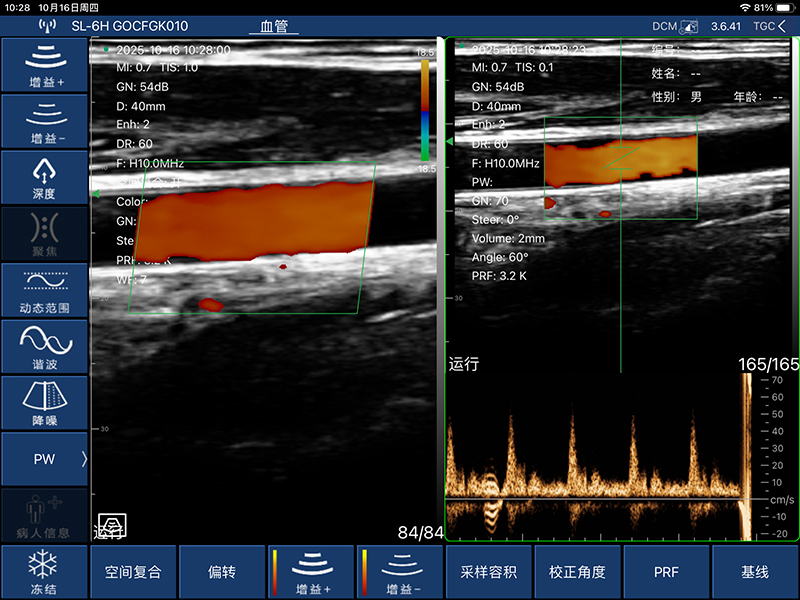

• 扫描方式:电子阵列扫描

• 探头频率:7.5/10MHz

• 扫描深度:20-100mm,可调

• 显示模式:B、B/M、Color、PW、PDI